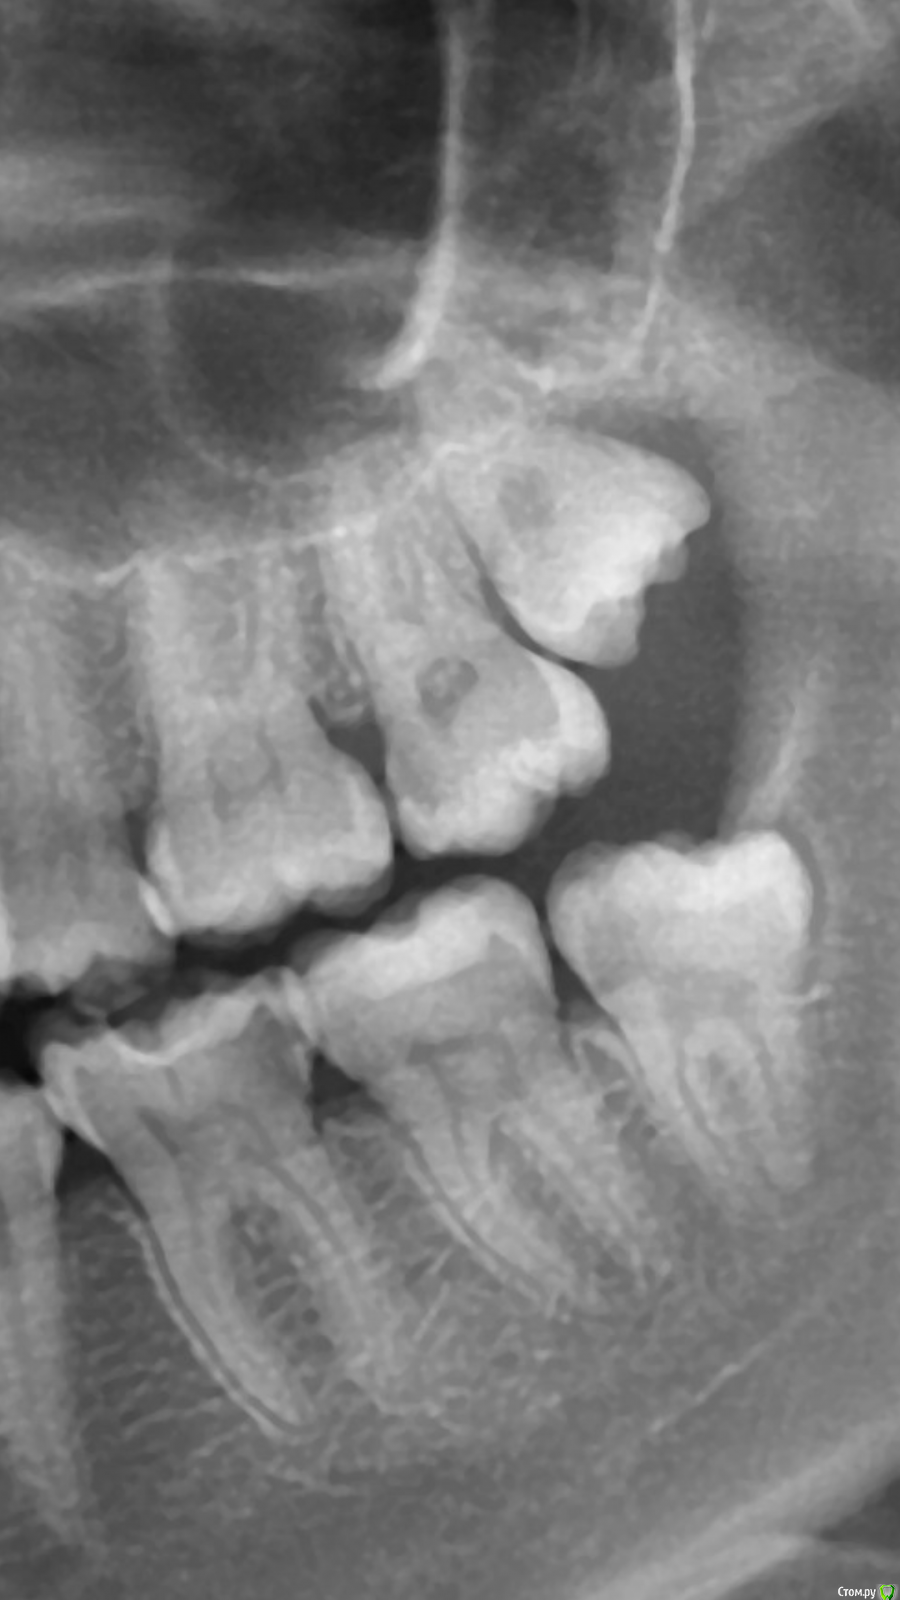

Malalejandra Опубликовано 1 февраля, 2017 Поделиться Опубликовано 1 февраля, 2017 (изменено) Добрый день!В последние несколько лет при чистке зубной нитью пространства между 6 и 7 верхними левыми зубами есть неприятное ощущение, как будто нить задевает нерв. Вечером начинает ныть, успокаивается, когда прочистишь нитью и прополощешь. Есть карманы с обеих сторон от 6ки. Два раза ходила к стоматологам,оба раза делали снимок, но ничего не нашли. Скажите пожалуйста, есть ли проксимальный кариес на снимке? Спасибо заранее! Изменено 1 февраля, 2017 пользователем Malalejandra Ссылка на комментарий

Malalejandra Опубликовано 1 февраля, 2017 Автор Поделиться Опубликовано 1 февраля, 2017 (изменено) а где снимок? теперь все есть. В первом сообщении - часть снимка панорамного, сделан ~3 года назад. Во втором - сегодняшний Изменено 1 февраля, 2017 пользователем Malalejandra Ссылка на комментарий

Malalejandra Опубликовано 1 февраля, 2017 Автор Поделиться Опубликовано 1 февраля, 2017 Спасибо, но, похоже, я немного сглупила, и сделала скриншот правой стороны панорамного снимка. Вот оба снимка, оба левые. Ссылка на комментарий